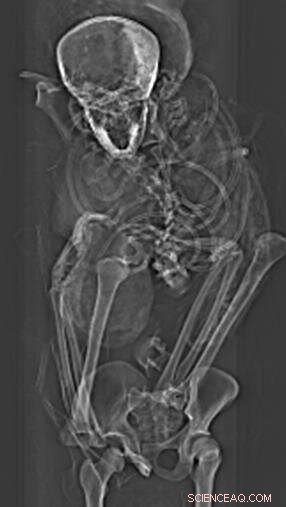

X ray of pharaoh Seqenenre-Taa-II's torso. Credit: Sahar Saleem

The authors of the new paper offer a novel interpretation of the events before and after the king's death based on the computer-processed X-ray images: Seqenenre had indeed been captured on the battlefield, but his hands had been tied behind his back, preventing him from defending against the attack.

These and subsequent examinations—including an X-ray study in the 1960s—noted the dead king had suffered several severe head injuries but no other wounds to his body. The prevailing theory, based on the evidence, was that the king had been captured in battle and then executed afterward, possibly by the Hyksos king himself. Others have suggested he was murdered in his sleep by a palace conspiracy.